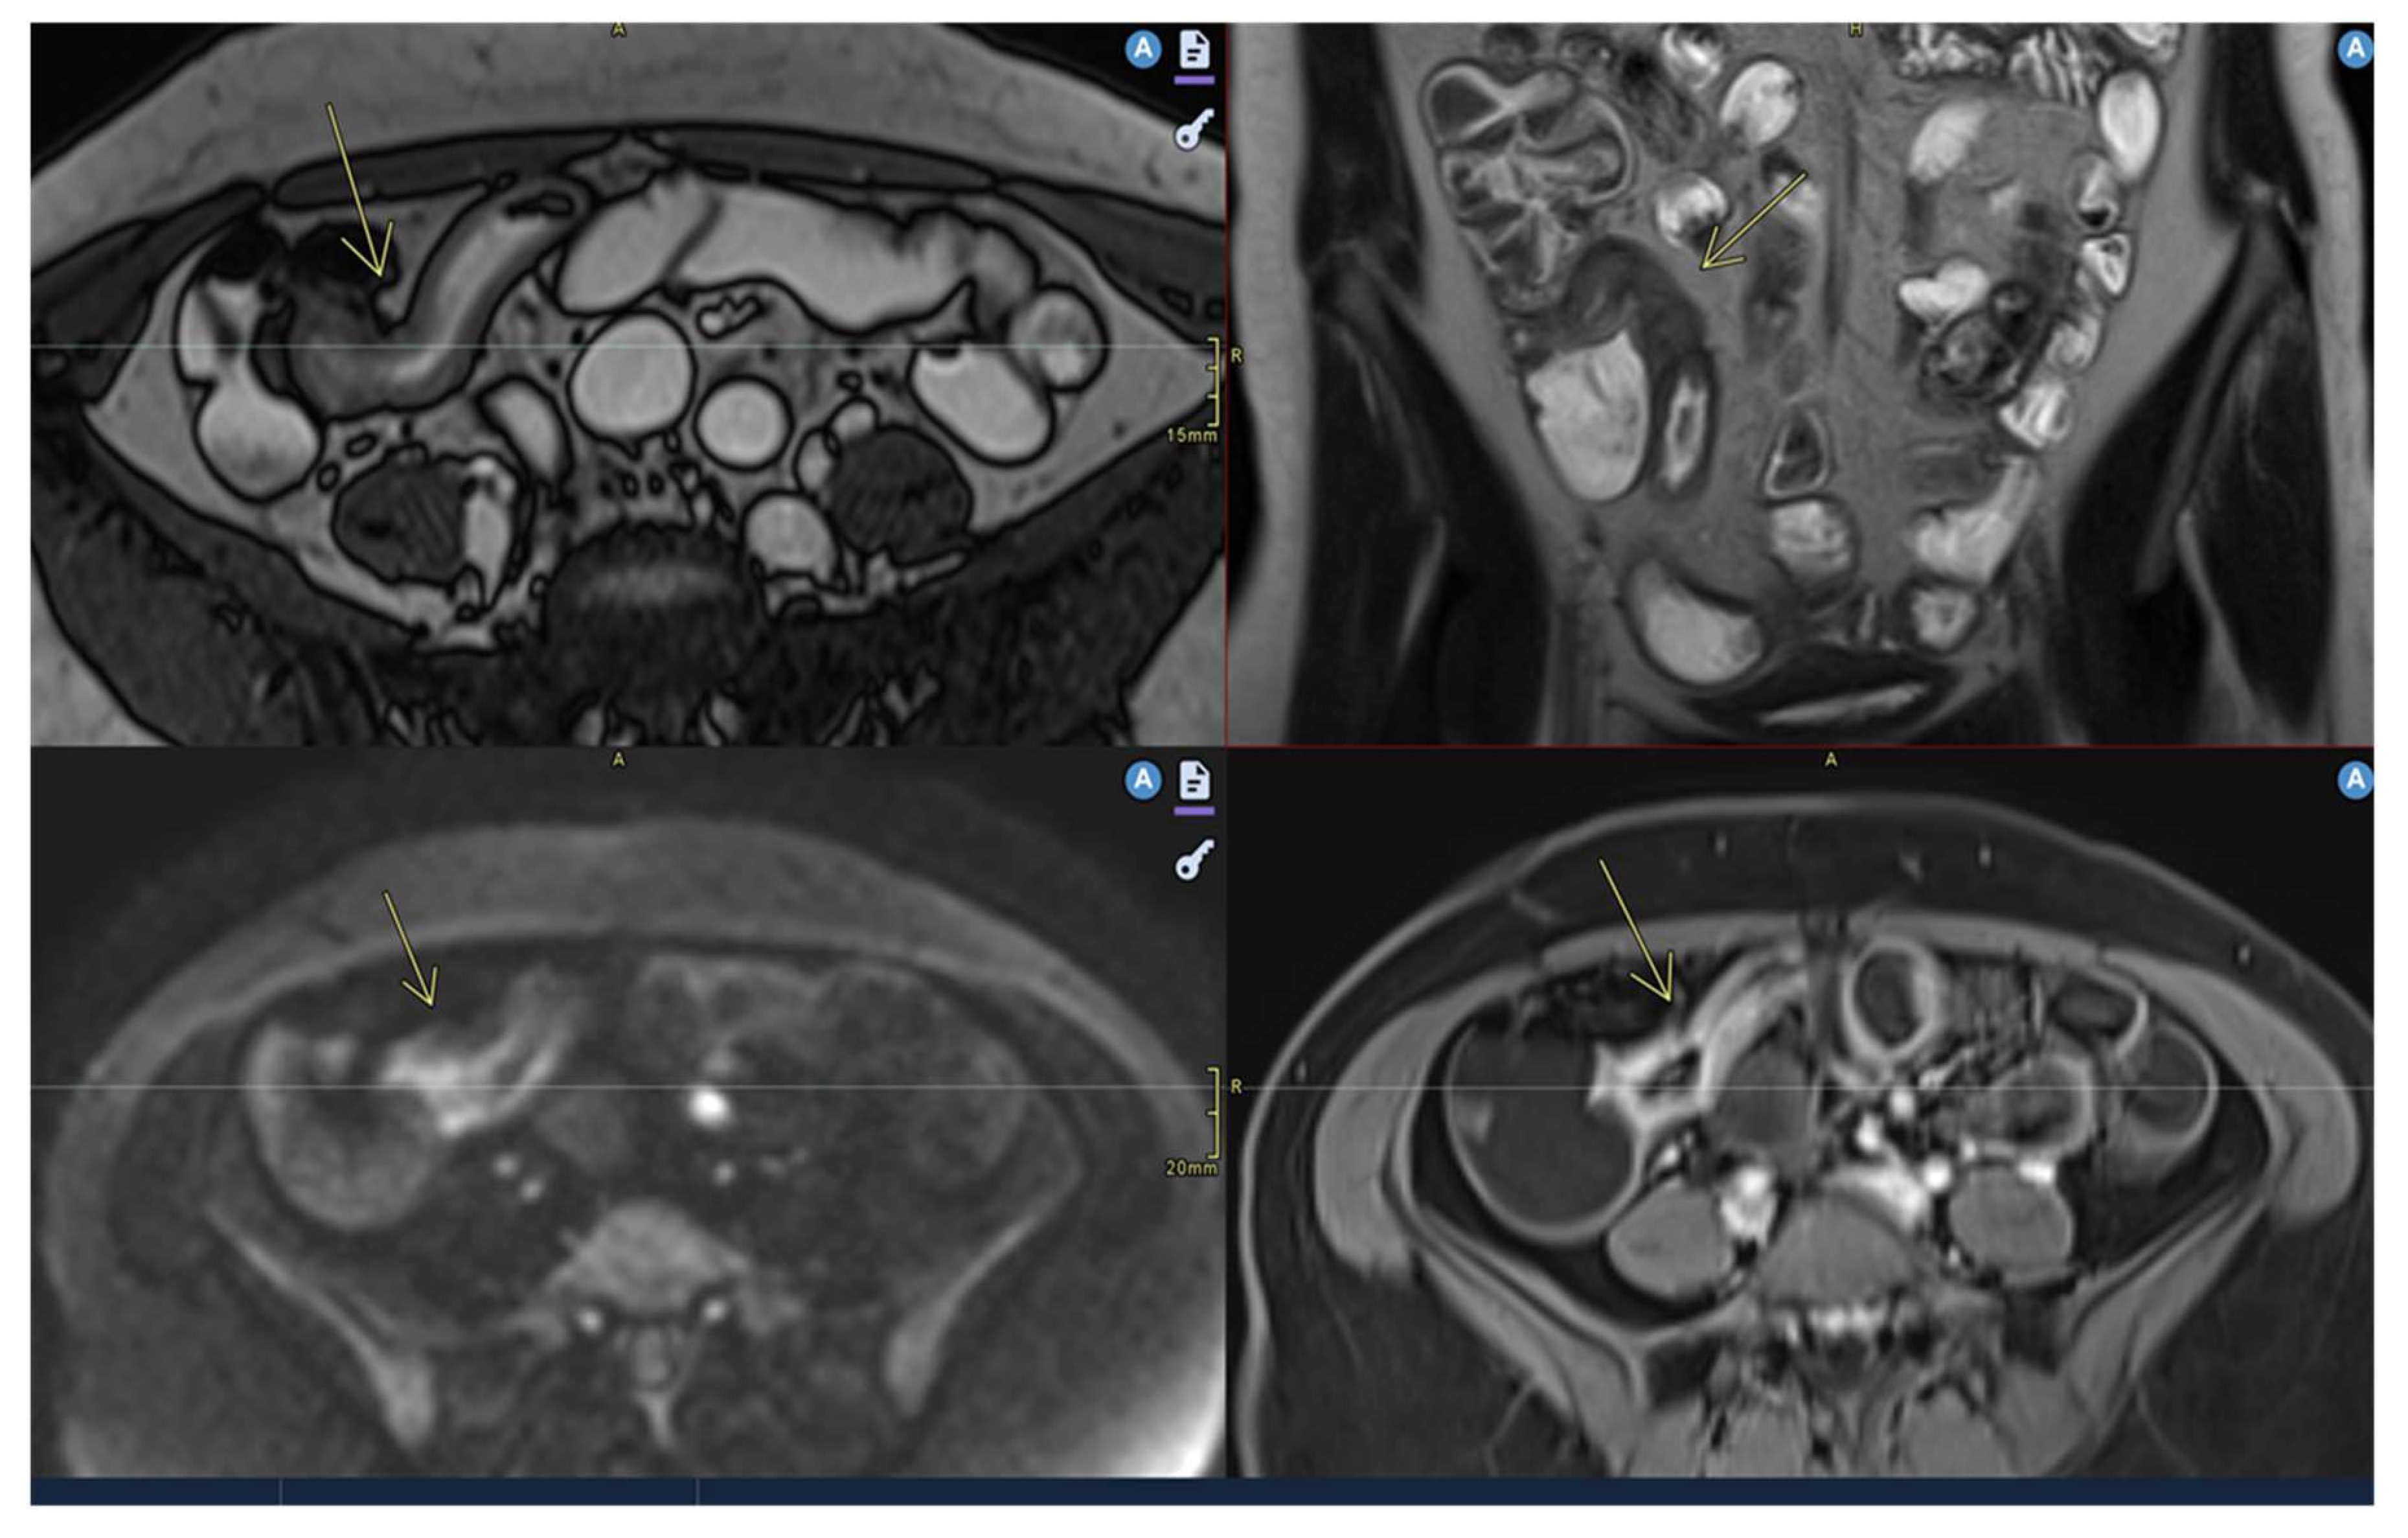

- Mural thickening :

- Is mild (<5 mm), moderate (<9mm) and severe (> 10 mm)

- Commonly occurs in active areas of inflammation (Figure 1).